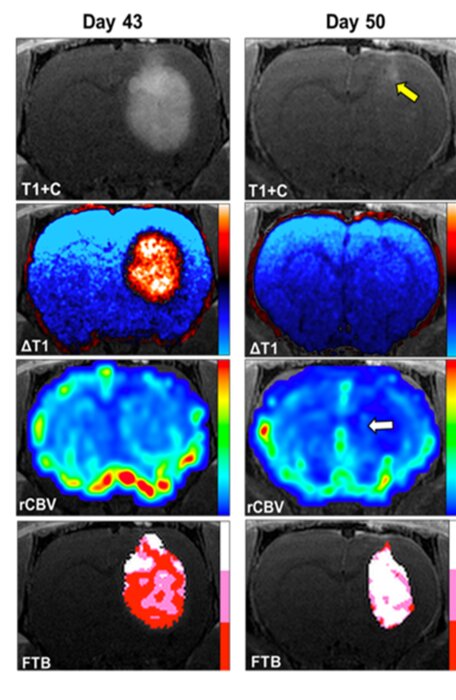

در تحقیقات پیش بالینی، دکتر چیتامبار و دکتر کاتلین اشمایندا کشف کردند که گالیوم مالتولات (GaM) هنگام تجویز داخل وریدی، بهطور قابل توجهی رشد گلیوبلاستوما را در مدل تومور مغزی موشهای صحرایی کاهش میدهد. تحقیقات بیشتر نشان داد گالیوم مالتولات که بهصورت خوراکی در موشهای حامل گلیوبلاستوما تجویز میشود، بهطور قابل توجهی اندازه تومورهای آنها را کاهش داده و بقای آنها را افزایش میدهد.